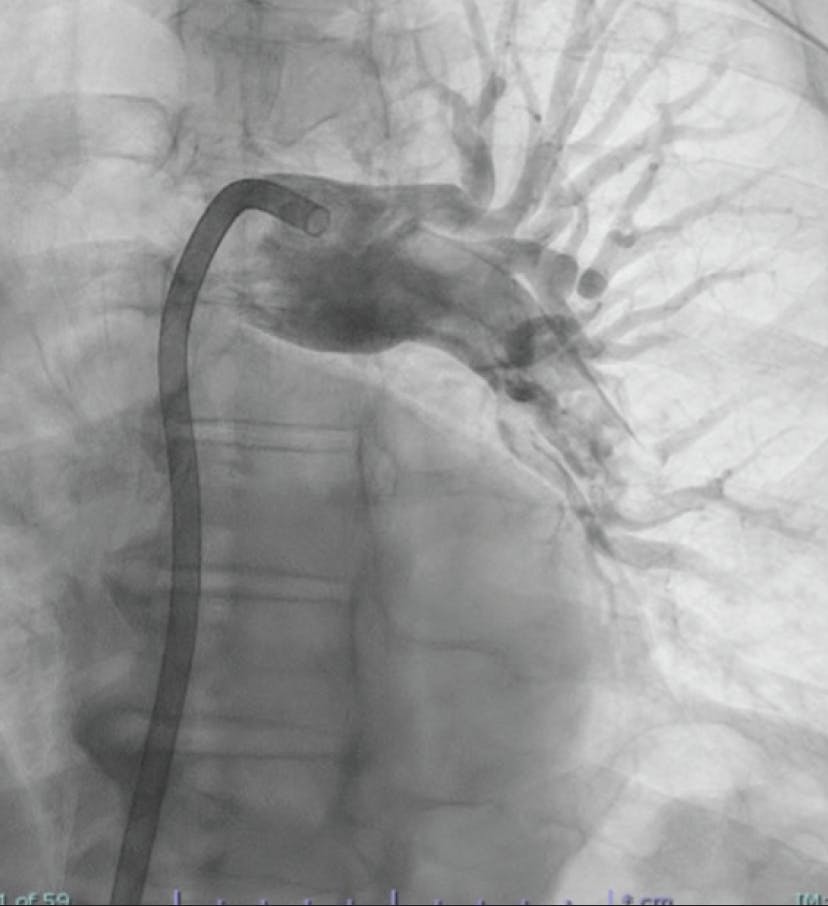

PATIENT PRESENTATION

A woman in her early 70s with a medical history of hypertension, hyperlipidemia, peripheral artery disease, type 2 diabetes mellitus, and a recent diagnosis of stage IV pancreatic cancer presented to the emergency department with hour-long chest pain and dyspnea, as well as cramping in the right calf. She underwent the CT pulmonary embolism (PE) protocol, which showed significant clot burden with a saddle PE extending into the bilateral main pulmonary arteries (PAs) (Figure 1 and Figure 2). Her lactate level was 8.2 mmol/L. She was started on a heparin drip and had evidence of hypoxia that required 3 L of nasal cannula. Initial vitals recorded a blood pressure of 117/82 mm Hg, heart rate of 96 bpm, SpO2 of 87%, and respiratory rate of 31 breaths per minute. There was evidence of right heart strain with a right ventricular/left ventricular (RV/LV) ratio of 1.4 by CT, as well as a high PE Severity Index. Given the large clot burden, marginal hemodynamics, and hypoxia, we decided to move forward with CAVT with Lightning Flash 2.0.

Figure 1. Initial angiogram of the left lobe.

Figure 2. Initial angiogram of the right lobe.

INTERVENTION

After achieving wire access, the Lightning Flash 2.0 was inserted. While in “Gallop Mode,” the saddle clot burden and subsequently the left and right main PAs were aspirated. Once the algorithm returned to “Sampling Mode,” aspiration was turned off and angiograms were obtained to assess the progress. After 5 minutes of aspiration, reperfusion of the main PAs and distal branches was achieved (Figure 3, Figure 4, and Figure 5), with improvement in the patient’s vital signs and no device-related complications.